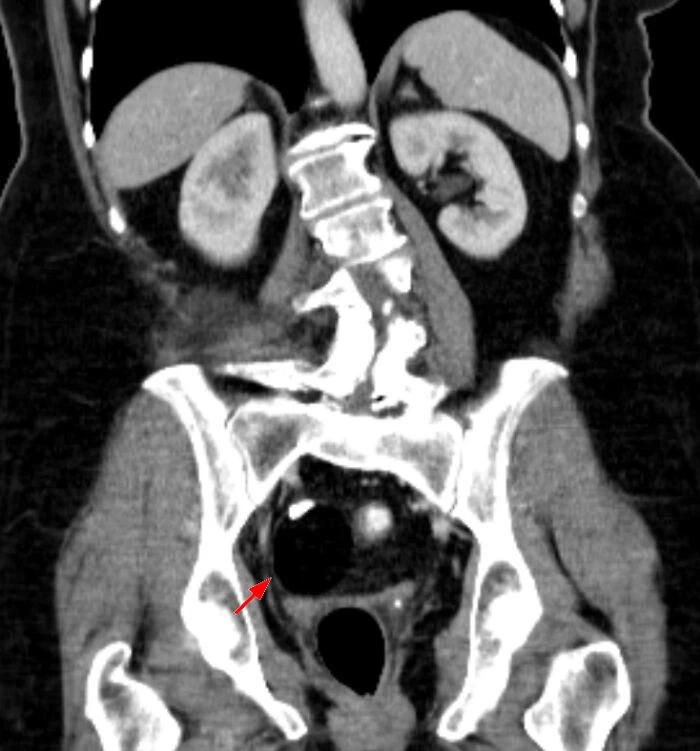

11. «Если ствол головного мозга (часть мозга, которая отвечает за моторный контроль всего тела) поврежден, может развиться синдром «запертого человека». То есть, человек полностью в сознании и осознает свое окружение, но не может двигаться или говорить. Единственные мышцы, которые остаются незатронутыми у большинства людей, — это мышцы, которые двигают глазами и веками. Вы, по сути, заперты в собственном теле, и единственным способом общения является моргание или движение глаз. Это может быть вызвано токсинами, закупоркой основной артерии, которая является основной артерией мозгового ствола, или другим повреждением ствола мозга».